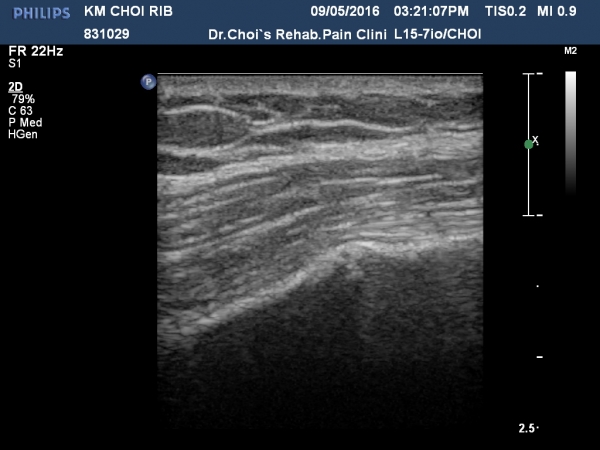

ÃÊÁø ½Ã °¥ºñ»À ÃÊÀ½ÆÄ°Ë»ç¿¡¼­ ÇÇÁú°ñ ¤·³à¼Ó¼º ¼Ò½ÇÀº º¸ÁöÁö ¾ÊÀ¸³ª

±æºñ»À Ç¥Ãþ¿¡ ±¹¼ÒÀûÀÎ ¿¬ºÎÁ¶Á÷ ºÎÁ¾ÀÌ °üÂûµÈ´Ù(»çÁø 1, 2, 3, 4).